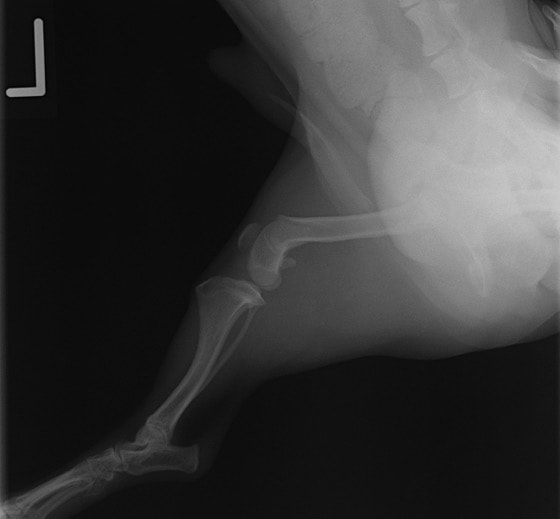

ペルシャ猫 11ヶ月齢 雄

他院にて左大腿骨遠位の成長板骨折(salter-harrisⅠ型)が認められており、治療相談を目的として来院。当院にて、キルシュナーワイヤーを用いたピンニングにより骨折部位の整復を行いました。術後の経過は良好で、現在も経過観察中です。

術前レントゲン